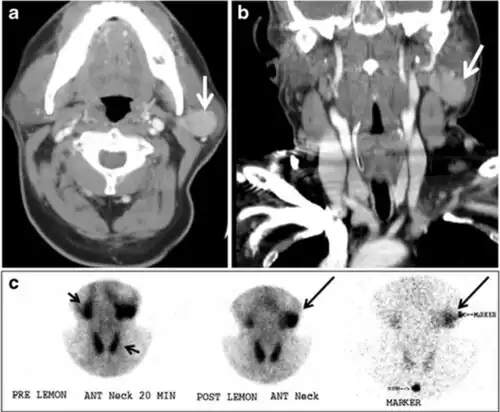

Fig. 17. Ectopic thyroid on the left parotid gland with a palpable left parotid mass in a 69-year-old male patient. a, b Axial and coronal enhanced neck CT scan demonstrates well-defined homogeneous enhancing mass (white arrows) within the left parotid gland with preserved surrounding fat planes. It also shows a normal thyroid in normal position in the lower neck. c Image taken 20 minutes after 5 mCi injected Tc99m-Pertechnetate shows normal thyroid uptake of tracer and physiological uptake in the salivary glands (short black arrow). There is a distinct focus of abnormal tracer accumulation in the left parotid/submandibular region. Patient was given lemon juice with evident normal washout from the salivary glands and relative retention by this abnormal focus (long black arrow).[1] -

Fig. 18. Lingular thyroid in a 33-year-old male who presented with oropharyngeal bleeding. an Axial enhanced neck CT scan at the level of mandible demonstrates a 3 × 3 × 3.4 cm round, partly well-delineated, heterogeneously enhancing lesion (white arrow). It is predominantly on the left side of the oropharynx and to some extent at the mid part of the base of the tongue. The thyroid gland was normal (not shown). b Image of the anterior face and neck taken 20 minutes after Tc99m-Pertechnetate injection shows absent thyroid radiotracer uptake in normal thyroid anatomical location (black short arrows). There is an area of increased uptake (long black arrows) corresponding to the posterior tongue mass identified on CT scan.[1]

Ectopic thyroid tissue may be detected in the tongue near the foramen cecum (90%) and along the midline between the thyroid isthmus and posterior tongue, lateral neck, mediastinum, and oral cavity. The most frequent location is the base of the tongue (Figs. 16, 1717 and and18).18). In 70% of cases, the ectopic thyroid is the only functional thyroid tissue present in the body (Fig. 18).[1]